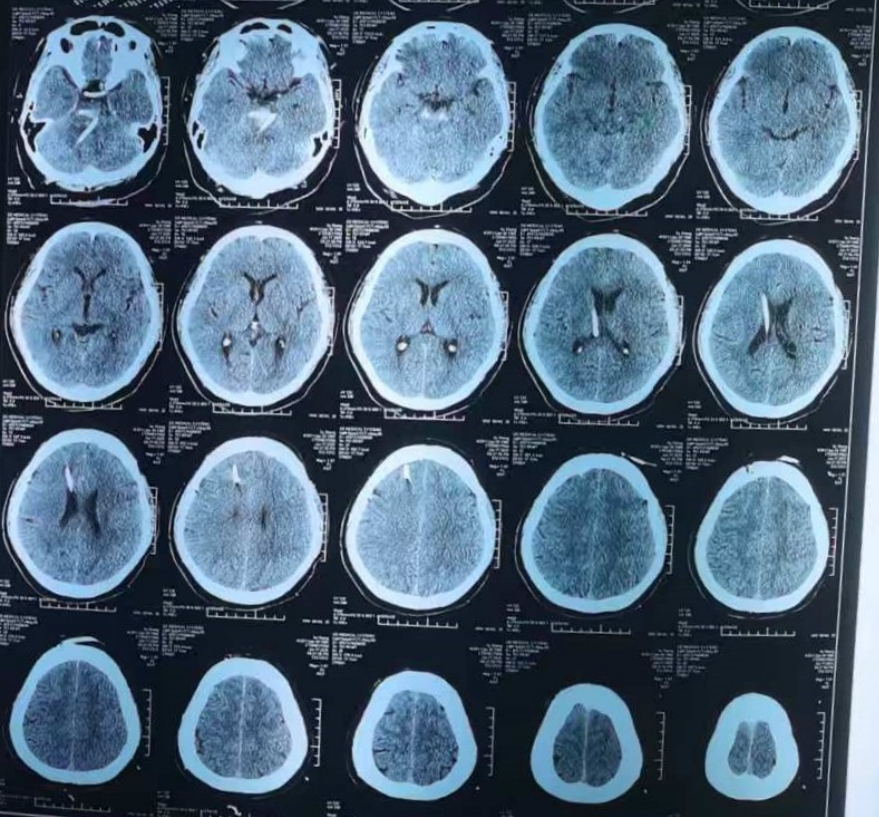

在详细说明手术治疗可能出现的风险和后果,取得家属的信任和同意后,由神经外科、麻醉科、放射科等科室通力协作,急诊全麻下行“立体定向颅内血肿穿刺引流术+脑室钻孔引流术”。手术顺利,术后患者逐渐恢复意识,右侧肢体可遵嘱活动,病情逐步平稳。

(术后复查CT:脑干血肿全部清除)